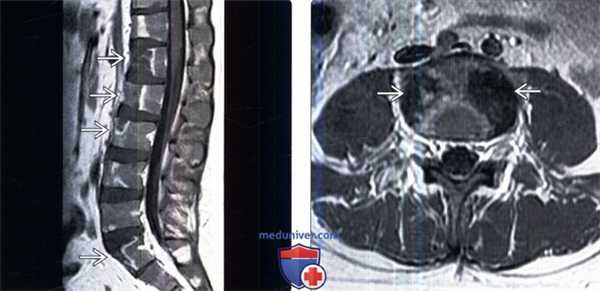

(Слева) Сагиттальный срез, Т1-ВИ с КУ, пациент с вновь установленным диагнозом лимфолейкоза: множественные четкие фокусы сниженного накопления контраста в телах позвонков. ограниченные зонами усиленного контрастирования. Мягкотканных образований в паравертебральной области или изменений межпозвонковых дисков не определяется.

(Справа) Аксиальный срез, Т1-ВИ с КУ, пациент с множественными инфарктами тел позвонков и вновь установленным диагнозом острого лимфобластного лейкоза: четко ограниченные очаги в боковых отделах тела позвонка с минимально выраженным контрастным усилением по периферии.

(Слева) Сагиттальный срез, Т1-ВИ: множественные инфаркты тел позвонков у пациента с острым лимфобластным лейкозом после проведенной химиотерапии. Обратите внимание на четко ограниченные зоны низкой интенсивности сигнала в передней половине тел позвонков.

(Справа) Сагиттальный срез, FS Т2- ВИ, этот же пациент: четкие зоны высокой интенсивности сигнала в передних половинах тел позвонков, аналогичные изменения видны в области крестца.